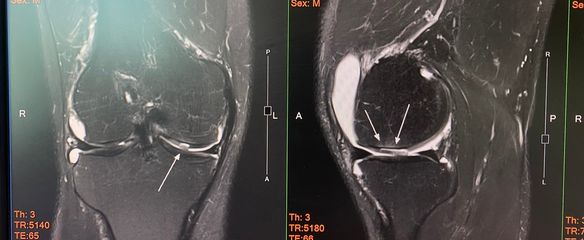

ซึ่งช่วงแรกคนไข้ทำได้ดีมากเลยครับ กลับไปเตะบอลได้หลายเดือน แต่พอเริ่มเตะได้ก็เตะมากขึ้นเวลาในการออกกำลังกล้ามเนื้อน้อยลง กลับมาบวมอักเสบอีกครั้งนึง เลยตัดสินใจส่งคนไข้ไป mri เพื่อดูความเสียหายของผิวข้อตามภาพประกอบ ตรงลูกศรจะเห็นว่า ผิวข้อเสียหายค่อนข้างเยอะ ทะลุลึกพอสมควรเลย รวมถึงมีตัวกระดูกอ่อนผิวข้อมีการหลุด แล้วคาขัดอยู่ในข้อด้วย ซึ่งอาจจะเป็นสาเหตุทำให้เหยียดเข่าได้ไม่สุด